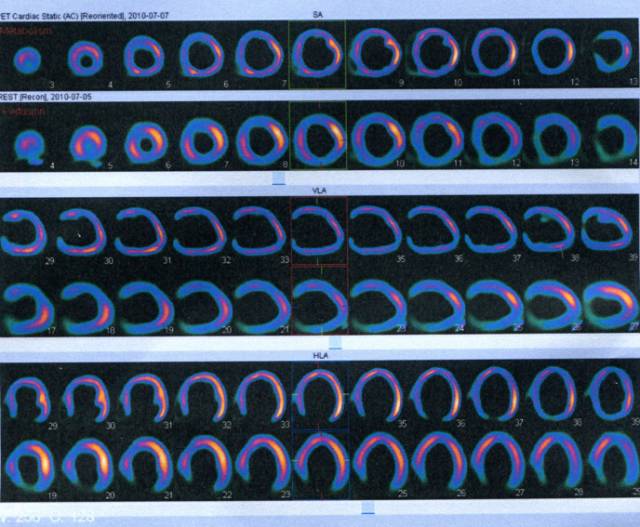

核素静态心肌灌注+PET显像

►左室心腔显著扩大,室壁运动弥漫减弱

►左室各节段血流灌注/代谢大致正常,放射性分布均匀,未见明显心肌受损

结论:支持扩心病改变